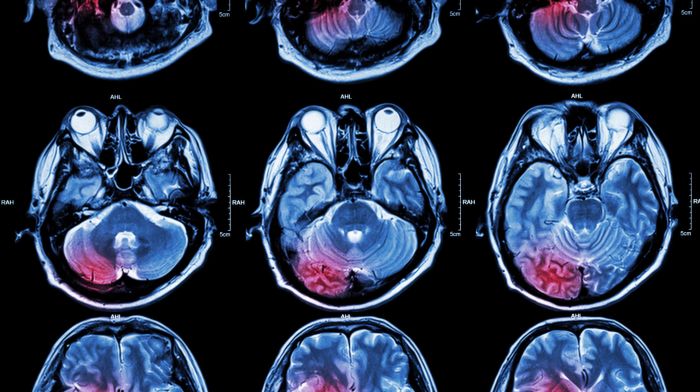

Неврология

Центр Минздрава РФ сообщил о регионах с низким доступом к реабилитации после инсульта

По итогам прошлого года почти в полутора десятках субъектов общее число получивших такую помощь не превышало 2—3%

Чрезмерное употребление алкоголя связали с развитием ранних и тяжелых инсультов

Кровоизлияния в головной мозг происходили на 11 лет раньше

Неврологические заболевания приводят к потере 11 млн жизней ежегодно

ВОЗ впервые опубликовала отчет о состоянии неврологической помощи в мире